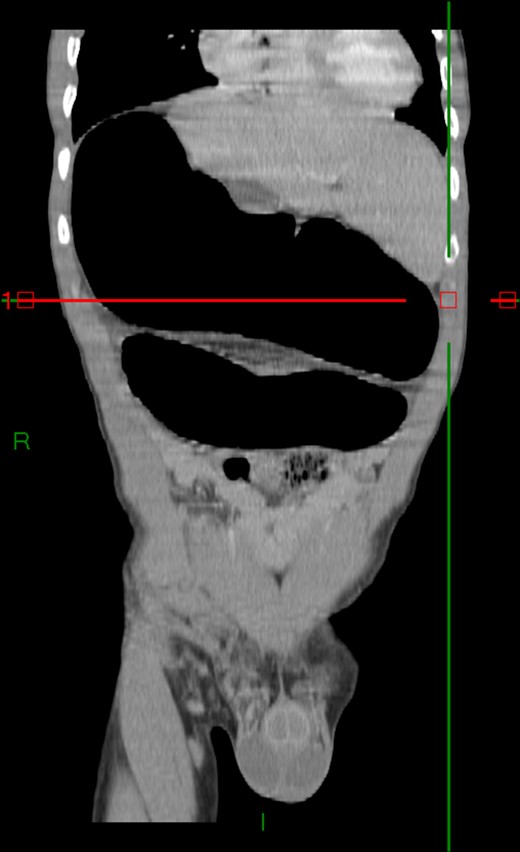

Case 1: A 40-year-old men, without previous abdominal surgery or history of abdominal trauma or peritoneal infections was admitted to the emergency department with generalized abdominal pain, nausea and vomiting. Physical exam revealed a distended abdomen, with pain in the epigastrium without tenderness. Laboratory investigation on admission was normal. Abdominal X-ray revealed a marked sigmoid colon distension suggestive of a colonic volvulus. A colonoscopy was conducted and revealed necrosis of the colon sigmoid apparently form a colonic volvulus. Abdominal-pelvic computerized tomography(CT) was conducted and a colonic volvulus associated with a transmesocolic hernia with transmural necrosis of the colon sigmoid was identified (Fig. 1). The patient was proposed to laparotomy during which a volvulus of sigmoid colon with transmural necrosis in a strangulated descendent transmesocolic hernia was identified. A Hartmann procedure was conducted and the patient was discharged at sixth post-operative day. At 2 year follow-up consultation, the patient remained free of complains, with the intestinal transit re-established.

Abdominal-pelvic CT—coronal plane: colonic volvulus associated with a transmesocolic hernia with transmural necrosis of the colon sigmoid.